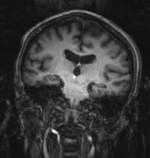

RegLib C14 unregistered.png MRI and PET before registration (click to enlarge)

RegLib C14 registered.gif MRI and PET after registration (click to enlarge)